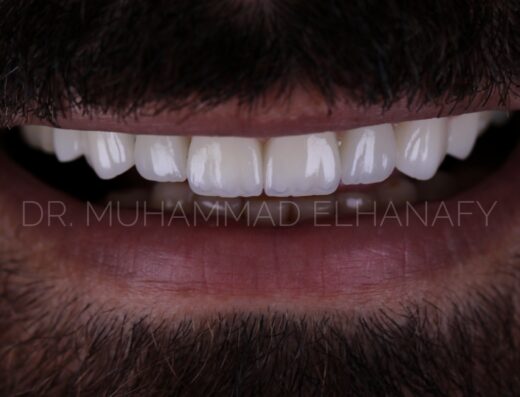

تحسين شكل الابتسامة بيعتبر خطوة مهمة في تجهيز العروسة أو العريس، وده بيخلي اختيار دكتور أسنان مناسب حاجة أساسية قبل المناسبة.

- تحسين شكل الابتسامة